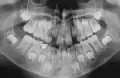

Будет или не будет у ребенка какой-либо зуб — легко узнать по панорамному снимку. Если зачаток есть — зуб будет, если зачатка нет, то зуба не будет и зачаток потом тоже не появится. Все зачатки видны на рентгене, так что его надо сделать в первую очередь и потом показать детскому стоматологу, он точно все увидит и скажет.